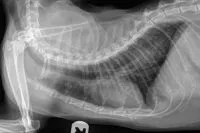

Xray of a cat with feline asthma.

A chest X-ray showing classic feline asthma lung changes.